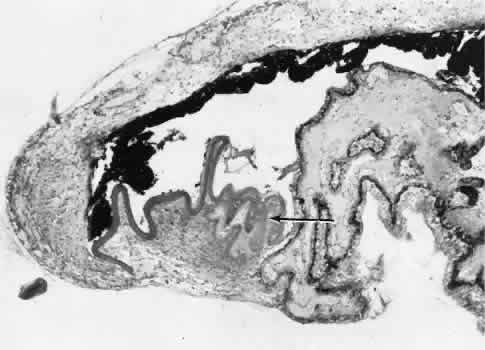

| All ocular surgical procedures are associated with potential complications. A